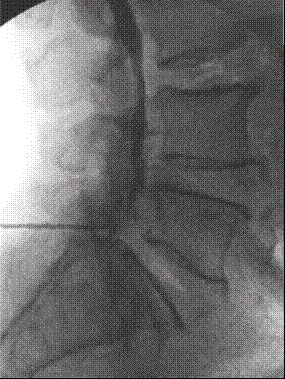

Previas asepsia y antisepsia en la zona lumbar e infiltración de la piel y el tejido celular subcutáneo con 3 mL de lidocaína simple al 2 % al nivel L5-S1, se avanzó una aguja Touhy n.º 17, se obtuvo pérdida de la resistencia al aire y se intentó acceder al espacio epidural L5-S1 (Figura 1). Se inyectó 1 mL de contraste no iónico (Omnipaque™ 300) y se obtuvieron luego imágenes fluoroscópicas del canal espinal lumbar en proyecciones AP y lateral (Figuras 1 y 2), en las que no se detectó anticipadamente un patrón subdural de la inyección por lo que se asumió la inyección epidural interlaminar L5-S1. Se procedió a inyectar en dicho nivel 10 mL de un preparado consistente en 80 mg de metilprednisolona más 10 mg de bupivacaína simple al 0,1 %, se retiró la aguja intacta y se trasladó al paciente a la sala de recuperación, con signos vitales estables, consciente y cooperando al cambio de posición hacia la camilla de transporte.

El diagnóstico de certeza del bloqueo subdural es radiológico 20. En el primer caso, guiado por fluoroscopia, se pudo observar, luego de la aplicación del medio de contraste, la distribución subdural en la proyección AP, como una extensa dispersión a varios niveles por encima y por debajo del sitio de inyección, con patrón homogéneo del contraste (Figura 1). En la proyección lateral (Figura 2) se observó una colección densa de medio de contraste con abombamiento a la porción central del canal espinal, que no salía a las raíces espinales laterales o a la porción inferior del saco tecal.